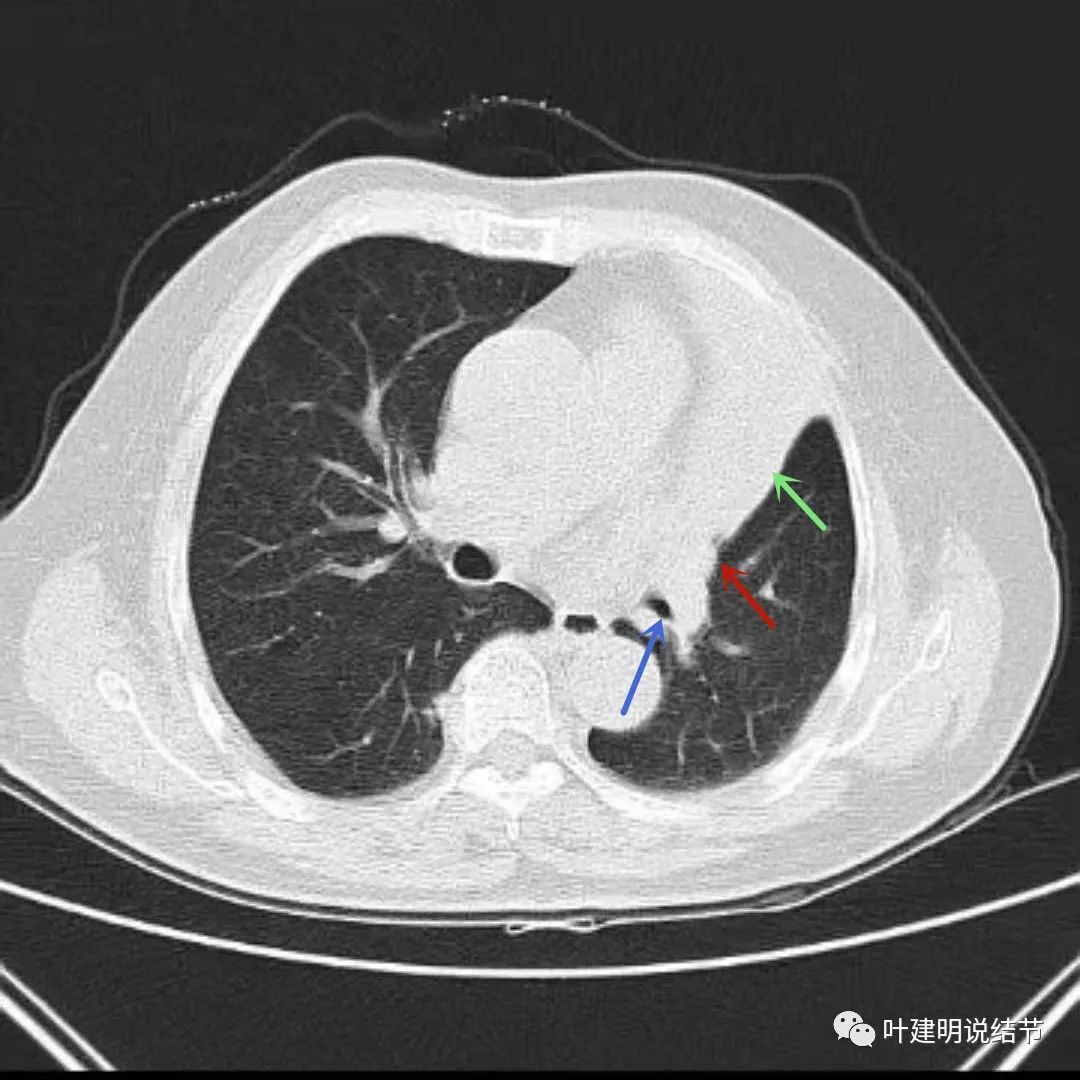

上图绿色箭头所指区域考虑不张的肺组织,红色箭头所指附近为肿瘤,且有膨胀性

上图绿色箭头所指区域考虑为肺不张,红色示肿瘤处,桔色箭头所指处是被肿瘤包绕的肺动脉分支